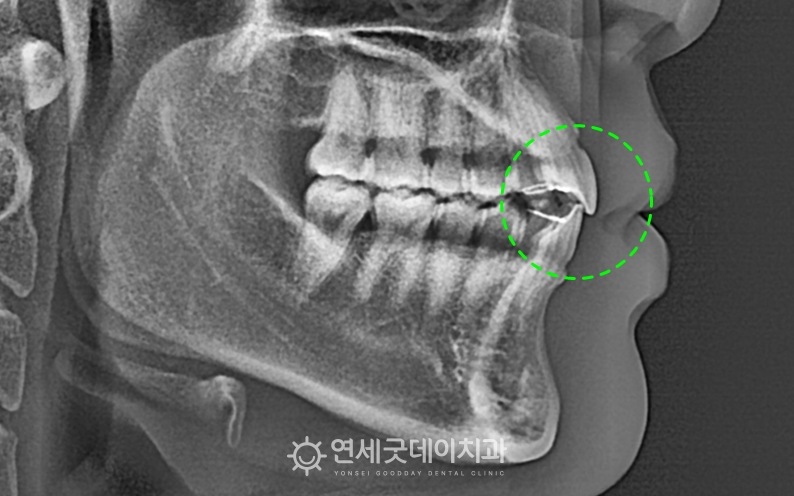

스플린트를 이용한 턱관절교정 후 교합이 일정해지고 환자분은 비발치로 진행되었으며 상하악의 구치부 함입을 ▲ 개방교합 교정 후 엑스레이 (촬영시기 : 2025년 7월) 1년 6개월 간의 인비절라인 교정이 종결되었습니다.